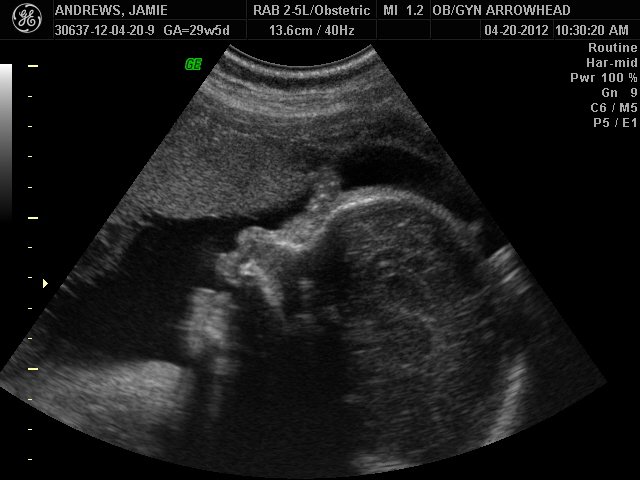

We offer complimentary 3D/4D Ultrasounds to all our OB patients around 30 weeks! The following photos are some examples of our work, shown with permission from our patients.